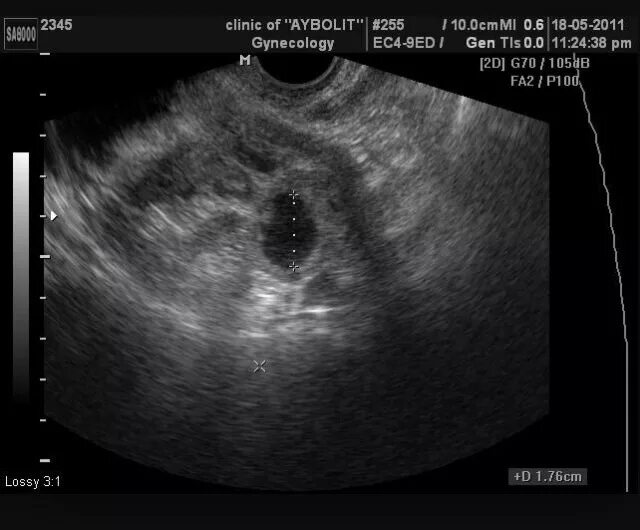

Что значит яичник не визуализируется на узи